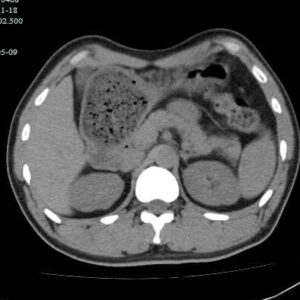

脂肪肝:症状、原因与治疗全攻略 脂肪肝是一种常见的肝脏疾病,其特征是肝细胞内脂肪堆积过多。据统计,全球约有25%的人群患有脂肪肝,且发病率呈上升趋势。本文将为您详细介绍脂肪肝的症状、原因、诊断、治疗和预防方法。 一、症状表现 脂肪肝的早期症状不明显,随着病情进展,可能出现以下症状: 早期:通常无明显症状,或仅有轻微的乏力、右上腹不适。 进展期: 右上腹疼痛:可为隐痛、胀痛。 乏力、疲劳:常与肝脏功能受损有关。 食欲减退:消化功能下降。 恶心、呕吐:肝脏功能受损的表现。 黄疸:皮肤、巩膜黄染,提示病情严重。 腹水:腹部膨隆,提示肝硬化。 其他:蜘蛛痣、肝掌、下肢水肿等。 二、发病原因 脂肪肝的发… 继续阅读